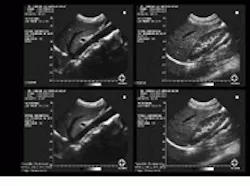

Busse set about linking the spatial sampling rate to the actual spatial resolution in ultrasound data to optimally obtain the highest spatial resolution with the fewest GF iterations. He developed a model of the lateral and axial resolutions. The model was developed as a function of transducer geometry, center frequency, and RF processor to determine the data and video sampling rates that should be applied before GF application. Upon usage, this model obtained effective speckle-noise reduction with a single GF application (see Fig. 1).

FIGURE 1. A geometric filtering algorithm developed by Lawrence Busse while at Tetrad Corp. reduces speckle noise in the ultrasound medical images of internal human organs. In one example, an original image of a scanned abdomen shows the liver and its surrounding area (upper left). The same image is reconstructed after applying geometric filtering (lower left). In another example, an original image depicts a kidney (upper right). The same image is restored via geometric filtering (lower right).